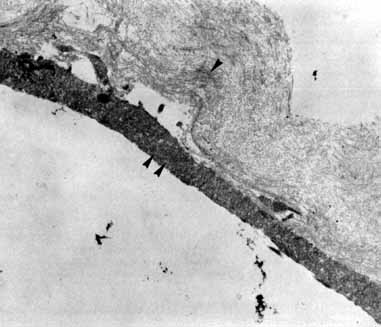

Tissue surgically peeled from the macular region in cases of impending macular hole has been found to be clinically consistent with posterior hyaloid. This finding was supported by electron microscopic examination of the tissue (Fig. 4).13,36 This observation is supported by the work of Kishi and Shimizu.37 They noted a large, optically empty space that appeared to be a complete posterior vitreous detachment in eyes with advanced liquefaction of the vitreous. They termed this area the posterior precortical vitreous pocket (PPVP). They found this pocket in 48 of 84 eyes with either an incomplete or no posterior vitreous detachment, and in 19 of 36 eyes with a posterior vitreous detachment. They noted that in eyes with advanced liquefaction of the vitreous, a large PPVP appeared to be a complete posterior vitreous detachment. In all of their postmortem cases, the posterior layer of the PPVP was found to be a thin layer of cortical vitreous. The presence of this PPVP strengthens the hypothesis that contraction of remaining attached cortical vitreous causes tangential traction on the macula, which gives the clinical appearance of an idiopathic macular cyst or hole.13,25,26,38 These impending holes or cysts' have been noted to resolve with spontaneous or surgical stripping of the membranes.13,25